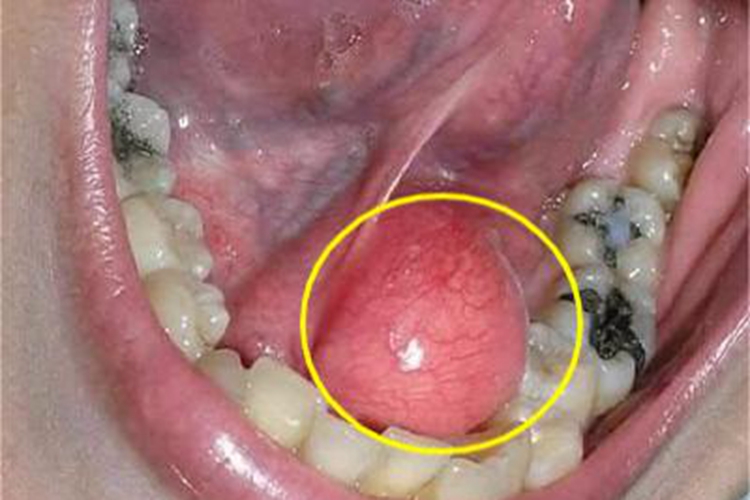

涎腺囊肿主要表现为导管囊性扩张,继之形成囊肿,检查可见患者口腔内出现包块,隆起于黏膜表面,大小不等,触之较柔软,有波动感,皮肤可呈蓝紫色或正常肤色,有感染时合并疼痛及压痛。

涎腺囊肿可发生在腮腺、颌下腺及舌下腺区,涎腺导管因炎症或结石阻塞使腺体分泌物潴留所致,阻塞原因多系损伤,有时多次反复损伤,可形成瘢痕而阻塞排泄管。